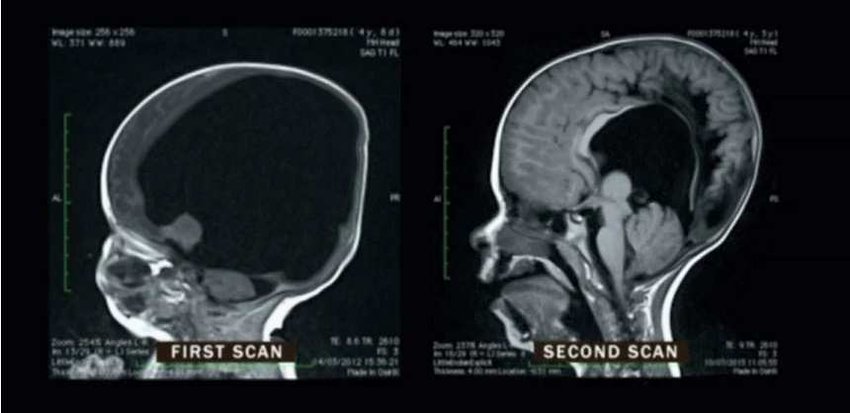

HIDRANENCEFALIA: sobrevivir sin el 98% del cerebro